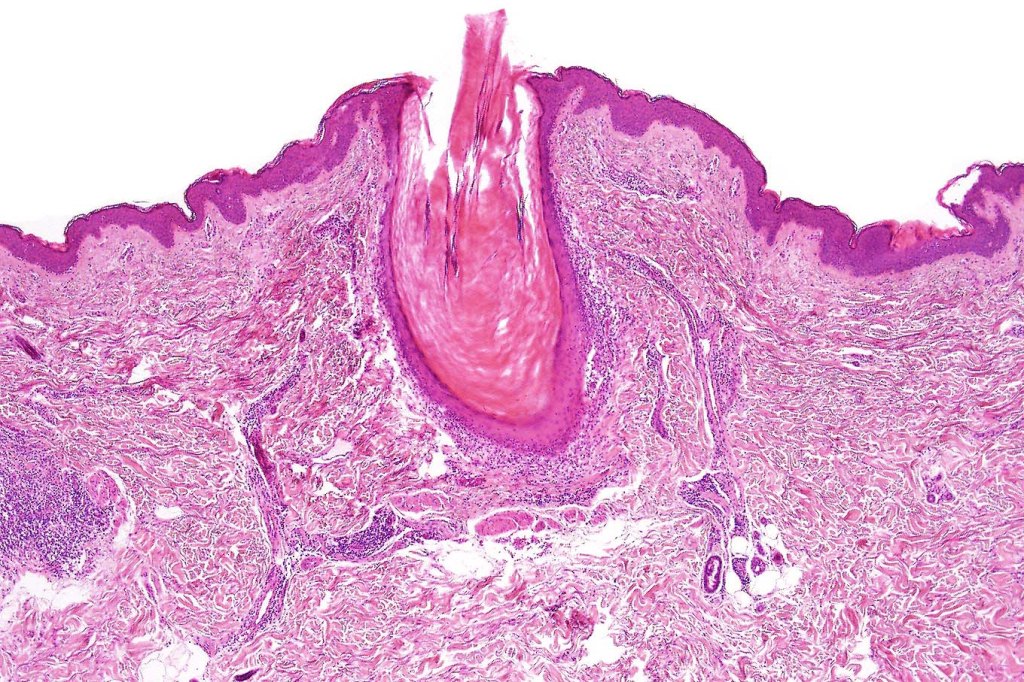

Histological features

•Epidermal involvement often absent

•Follicular infiltration by atypical lymphocytes & Sézary cells

•+/- basaloid follicular hyperplasia